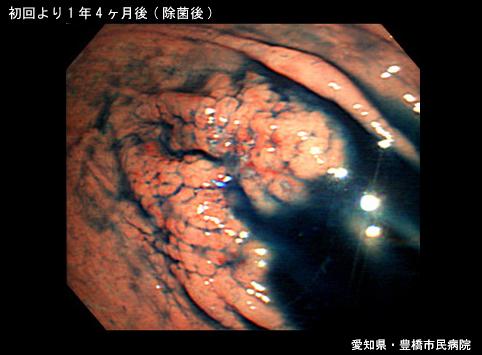

A case of gastric MALT lymphoma in which radiation therapy was effective.

Aichi Pref., 豊橋市民病院 (豊橋市民病院, Dr. 後藤)

Malignant Lymphoma/Malignant lymphoma

Stomach/Body

Endoscopy

Type 0/IIa (IIa+IIc) Superficial elevated and depressed type

25 - 29